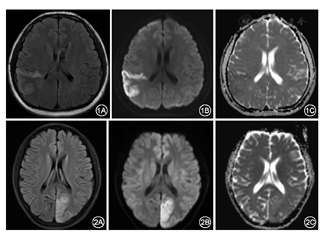

46例行常规MRI检查显示病灶呈长T1、长T2信号影,FLAIR呈高信号,其中42例仅累及皮质及皮质下白质,4例同时累及基底节区。46例中累及顶叶26例(56.5%)、枕叶25例(54.3%)、颞叶23例(50%)、额叶13例(28.3%)、岛叶8例(17.4%)、基底节区4例(8.7%)。复发病例14例,脑内病灶与以往相似,但部位有变化,呈现新旧交替状态。21例新旧病灶并存时期,DWI呈高信号,ADC图高和低信号并存(表1、图1,图2);12例新病灶DWI呈高信号,ADC图呈高信号(图2);13例陈旧性病灶DWI呈高信号,ADC图呈低信号,局部脑组织萎缩,皮质变薄,脑沟增宽。20例行MRI增强扫描,18例不强化,2例可见轻度沿病变脑回分布的线样强化。46例行MRA检查,均无明显血管狭窄。46例患者行PWI检查,其中33例呈灌注增高,11例呈灌注减低,2例灌注正常(表1、图3)。

MELAS好发于脑的后部(枕叶、顶叶或颞叶),少数累及基底节区、丘脑、小脑、脑干及额叶,一般局限在皮质及皮质下白质区,深部白质较少受累,呈脑回样异常信号影[6]。病变分布区与正常脑动脉血管供血区并不一致。病灶可单发或散在多发,多为不对称分布,随病情进展,病灶区有进行性加重和对称性趋势,动态MRI检查可成游走性、多变性的特点,此特点可与脑梗死鉴别。对于反复发作、病程较长的,可出现局部脑皮质萎缩,皮质出现层状坏死[6]。该组病例中复发病例复查MRI,病灶特点与上述文献报道相符。病灶区T1低信号,T2高信号,FLAIR呈高信号影。DWI呈高信号影,ADC值可升高、正常、或者减低[7]。该组病例急性期DWI呈高信号,ADC图呈高信号;慢性期DWI呈高信号,ADC图呈低信号,急慢性病灶并存时期,DWI呈高信号,ADC图高和低信号并存。该特点与上述文献一致。MELAS增强扫描多不强化或仅见轻度沿病变脑回分布的线样强化。急性期病变部分可见轻度线状脑回样强化,Yonemura等[8]认为可能是血-脑屏障破坏和高灌注引起的局部渗出或循环障碍所致。慢性期病变呈软化灶样改变,病变区及病变边缘无强化。该组20例患者行MRI增强扫描,18例不强化,2例可见轻度沿病变脑回分布的线样强化。MRA检查无明显血管狭窄等相关征象。文献中也有MELAS慢性期出现大血管狭窄、分支减少改变的报道[9,10],该组病例中MRA均无异常。